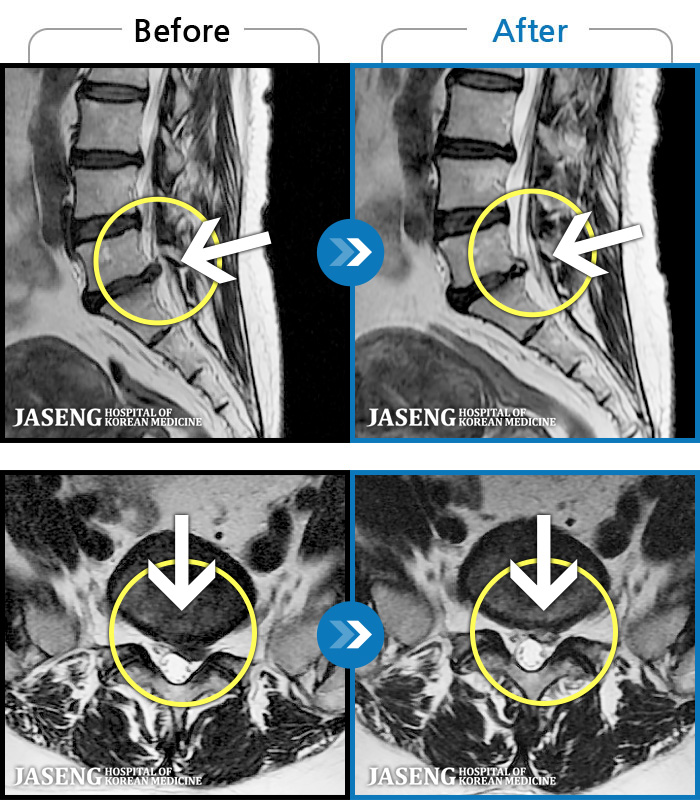

- MRI ġ

MRI ġ

1,304 MRI ũ ʸ Ȯϼ.